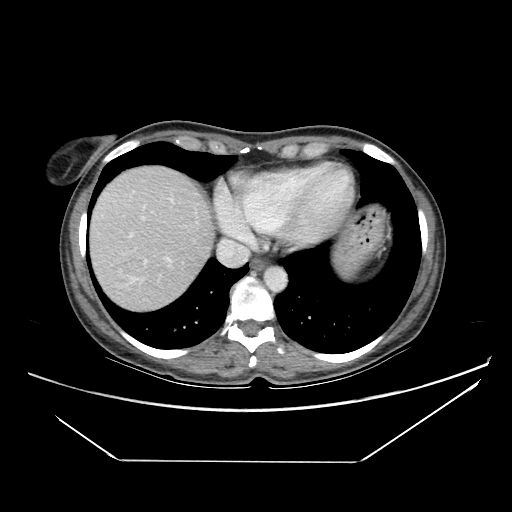

Original NATIVE CT scan (input)

Full window (WL 1023.5, WW 4095 β†’ Low βˆ’1024, High +3071)

Generated VENOUS CT scan (A→B translation)